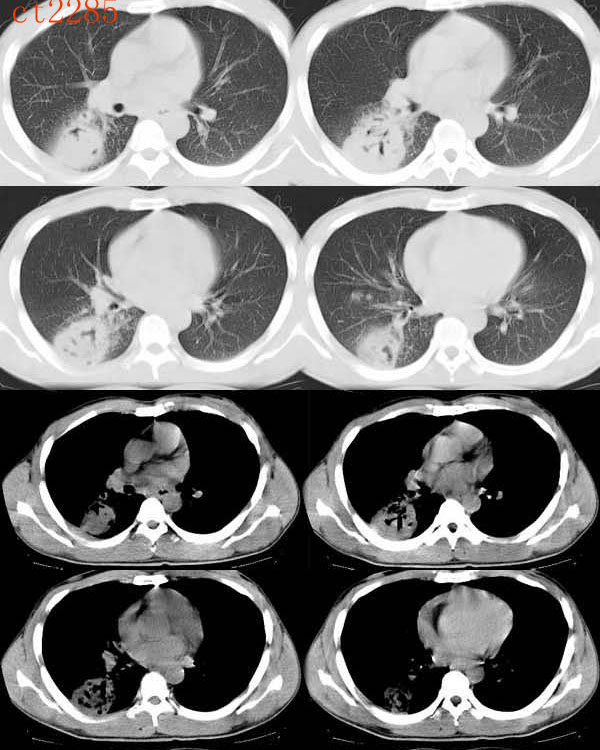

(1)发生部位:炎性假瘤可发生在两肺的任何部位,但多位于肺的表浅部位,邻近胸膜处或者靠近叶间裂。可以跨叶生长,原因可能是跨叶浸润的炎症使得假瘤跨叶融合的结果。

(2)假瘤形态:炎性假瘤的形态不一,可呈圆形.椭圆形或类圆形,也可呈驼峰状或不规则图形。

(3)假瘤大小:多数假瘤的直径在2-4cm,也可大于5cm,少数甚至大于10cm.

(4)假瘤密度:炎性假瘤一般为中等密度,密度均匀。而脓性炎症形成的假瘤则有时可见小空洞。空洞可以单发也可多发。少数瘤体切开时可见脓性物。

(5)假瘤边缘:

①有假无假性包膜者边缘清楚。有的由于肿块不规则可表现分叶状。

② 无假性包膜者,假瘤周围有纤维化和多种细胞成分侵润,表现为片状、边缘模糊的团块状影。或有轻度的渗出性病变,边缘模糊,以组织细胞围增生型多见。有的假瘤周围还可以出现类似周围型肺癌的放射冠状表现。

(6)邻近改变:位于肺周边部的假瘤,其邻近胸膜可见局限性粘连增厚。位于近肺门区的假瘤,偶可阻塞支气管,形成肺叶不张而将假瘤包裹,甚似中央性肺癌,但不出现肺门或纵膈淋巴结肿大。